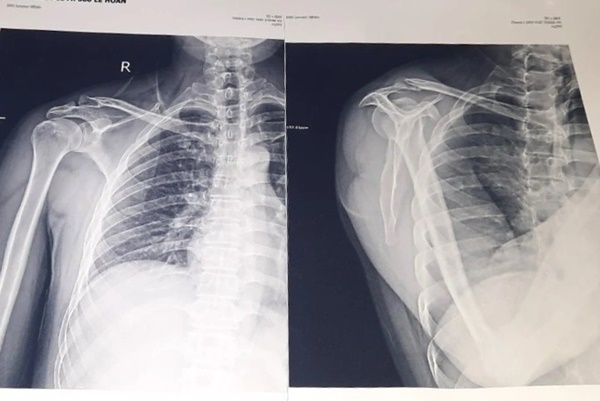

Hình ảnh chụp phim X-Quang cho thấy anh D. bị gãy xương đòn vai (Ảnh: NVCC).